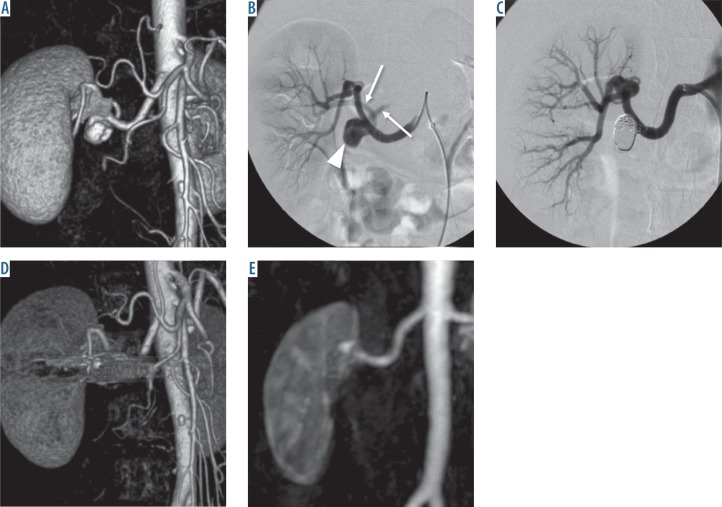

Figure 2.

A 56-year-old woman with a right renalaneurysm. A) Computed tomography angiography (CTA) demonstrated an 11-mm aneurysm at the hilum of the right renal artery. B) Digitalsubtraction angiography showed a narrow-neckaneurysm (arrowhead) at the main trunk ofthe right renal artery and two efferent branches (arrows). C) It was treated by aneurysmal coilpacking. D) On CTA 39 months after the treatmentenhancement of the aneurysm was difficult toevaluate due to prominent metal artefacts. E) Ontime-resolved magnetic resonance angiographythe aneurysm was not enhanced and thus wasdiagnosed as occluded